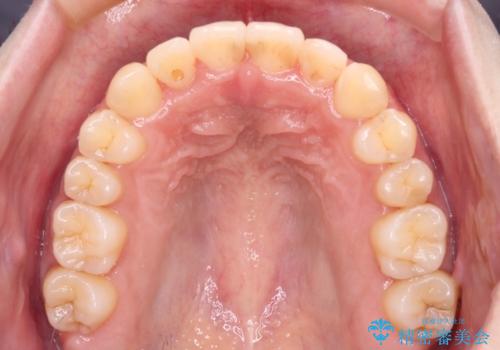

- 1年7ヶ月

より治療を速やかに行うため、上顎右側にアンカースクリューを使用し、目標としていた1年半ほどで治療を終えることができました。